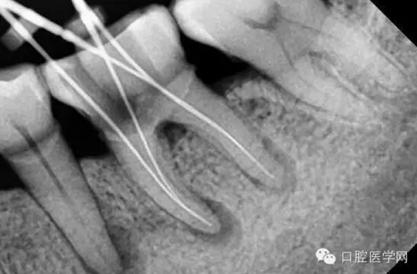

特殊情況可以插針拍片確定工作長(zhǎng)度(一般我比較相信根測(cè))

》工作長(zhǎng)度的確定。

》逐步后退法預(yù)備。

》逐步深入法預(yù)備。